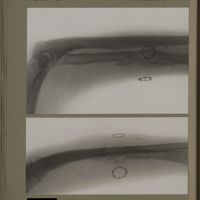

0123 - Page 11 - [Radiographies de l'épaule]0123 - Page 11 - [Radiographies de l'épaule]